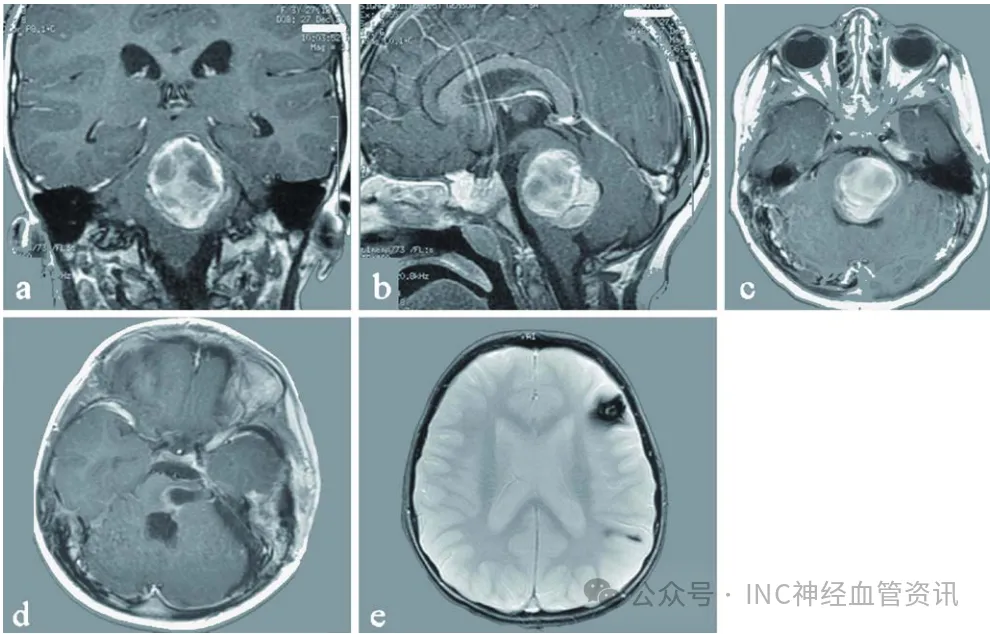

滴滴滴神经外科手术室内,正在进行一场艰难的开颅手术。患者是一名16岁的少年,巴教授正在一点一点地切除他脑干中如同豆腐渣般遍布的海绵状血管瘤。 我们之前问过很多医生,都说手术最...